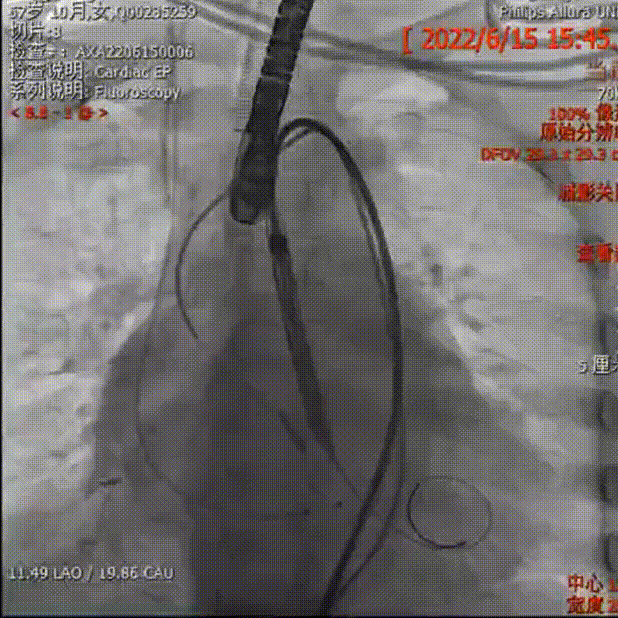

检查挂角

导丝跨瓣

测术前压差

AV29瓣膜定位